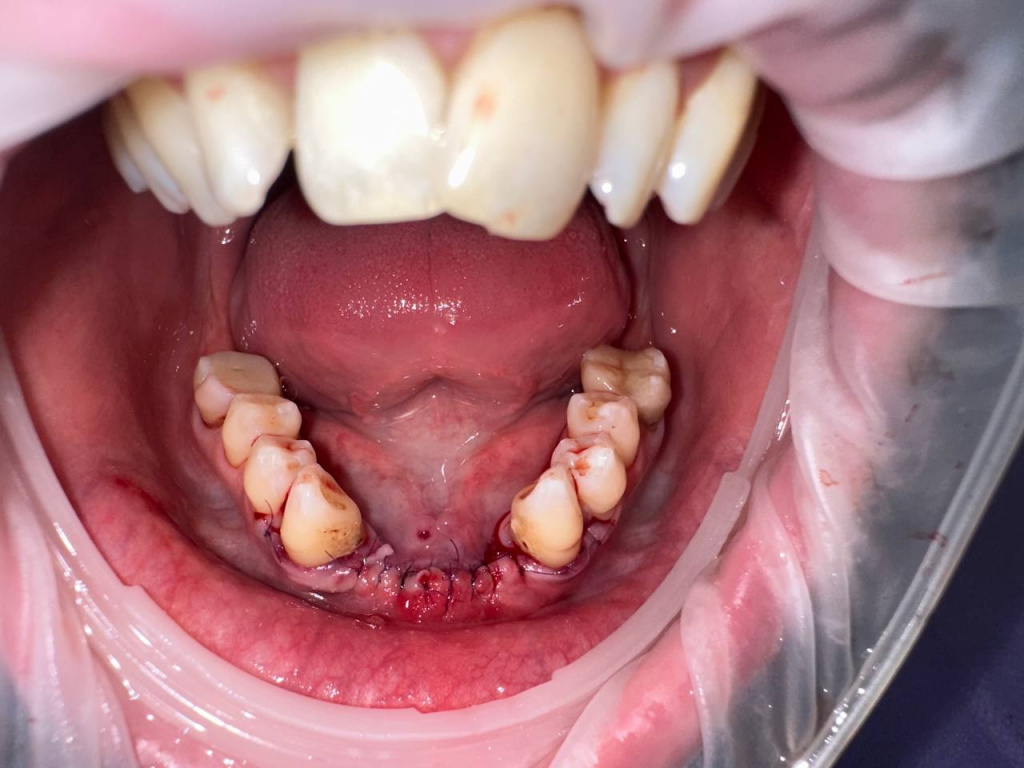

Уже много лет использую в своей практике имплантаты IMPRO. В этот раз мне предоставили линейку IMPRO Respect нового дизайна с широкими лепестками резьбы по отношению к телу имплантата. За счет чего получилось установить имплантаты в переднем отделе в узком гребне и с плохим костным предложением пациента. Ни разу не сталкивалась с осложнениями или проблем с имплантатми IMPRO Implantem. В этот раз не было исключением, была проведена операция через навигационный шаблон, имплантаты стабилизировались с хорошим торком. Хирургический набор и протоколы достаточно просты и удобны. Будем ждать ортопедической части, спустя месяц имплантаты стоят хорошо!

Пациент — мужчина 54 года.